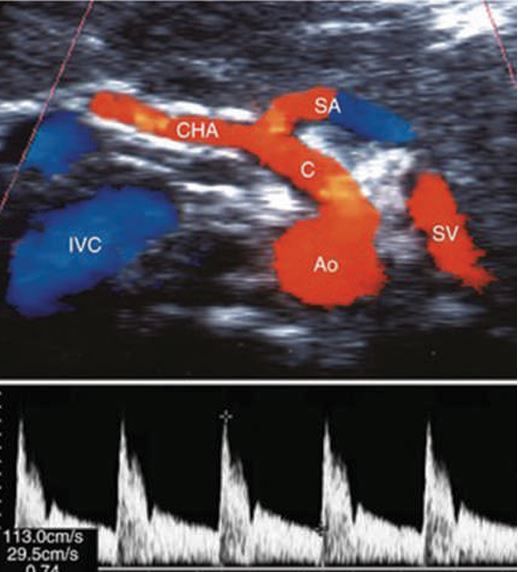

seagull sign

Source: The hepatic artery originates from the celiac trunk (a branch of the aorta) and supplies oxygen to the liver tissue.